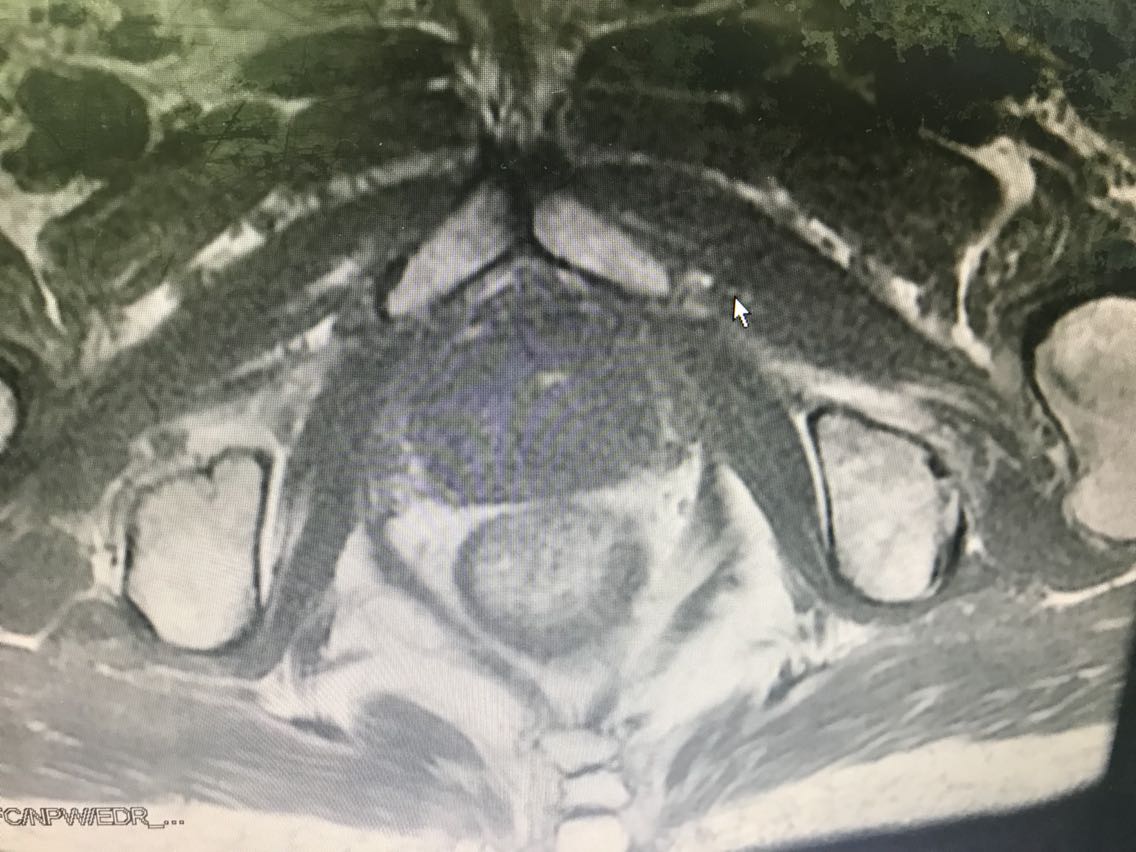

患者男性,77岁。 主诉:血尿7+月 现病史:入院前7+月,患者出现血尿,于外院体检查示PSA升高(10.62),服药血尿控制(具体药物不详),无尿频、尿急、下腹疼痛等不适,为求进一步诊治于我院门诊就诊,查前列腺MRI:前列腺尖部右侧中央带结节及9-10点结节,多系前列腺癌。门诊行前列腺穿刺活检示:编号1、2、3、4、5、6查见前列腺腺癌,Gleason评分4+3=7分。门诊以“前列腺癌”收入我科。患病来精神、睡眠、食欲可,大小便无异常,体重无明显变化。 既往史无特殊。

查体:腹部平软,无压痛及反跳痛,双肾及输尿管走行区无压痛,肾区无叩痛。直肠指检:前列腺Ⅱ°大,双侧质硬,右侧叶扪及约1cm硬结。 辅助检查: 前列腺MRI(2018-6-14,本院):前列腺尖部右侧中央带结节及9-10点结节,多系前列腺癌,累及右侧外周带 前列腺穿刺活检示(2018-6-28,本院):编号1、2、3、4、5、6查见前列腺腺癌,Gleason评分4+3=7分。